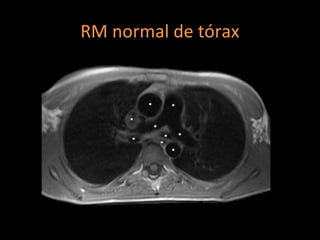

Ressonância magnética

Além de medir o diâmetro da artéria pulmonar:

Pode visualizar a direção e a velocidade do fluxo

sanguíneo nas câmaras cardíacas e nos grandes

vasos, obtendo imagens precisas das estruturas

cardiovasculares;

Técnica de escolha em longos seguimentos;

Diagnóstico de hipertrofia do VD e dilatação das

artérias pulmonares;

RM normal de tórax